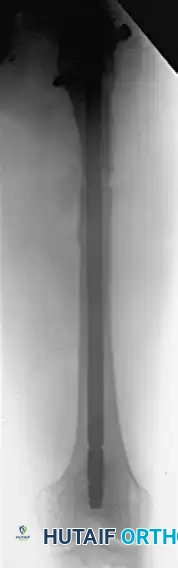

FIGURE 58-24 C: Postoperative AP radiograph following corrective osteotomy, removal of the previous implant, and rigid fixation with a proximal interlocking Grosse-Kempf medullary nail.

FIGURE 58-24 D: Postoperative lateral radiograph confirming restoration of sagittal alignment and rotation.